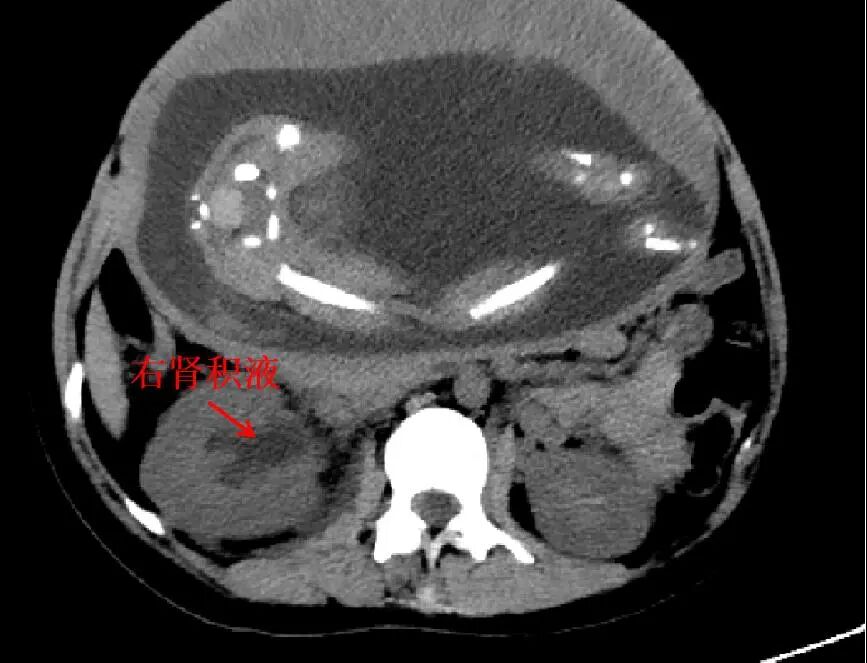

入院经详细检查后发现,林女士的右输尿管中上段、右肾积水,肾周及输尿管周围积液,未见明显阳性结石。考虑到患者是位孕妈,医生开始建议先采用保守治疗,但止痛效果欠佳,于是产科邀请泌尿外科前来会诊。

妊娠期间更易出现肾积水,尤其是右侧生理性肾积水,因为逐渐增大的子宫会使得肾脏和中上段输尿管无症状扩张。症状一般表现为:背部、腹部或侧腹区域急性疼痛,恶心和呕吐,持续尿路感染与尿痛、尿中带血、尿频,胸痛,下肢肿胀,发烧等。